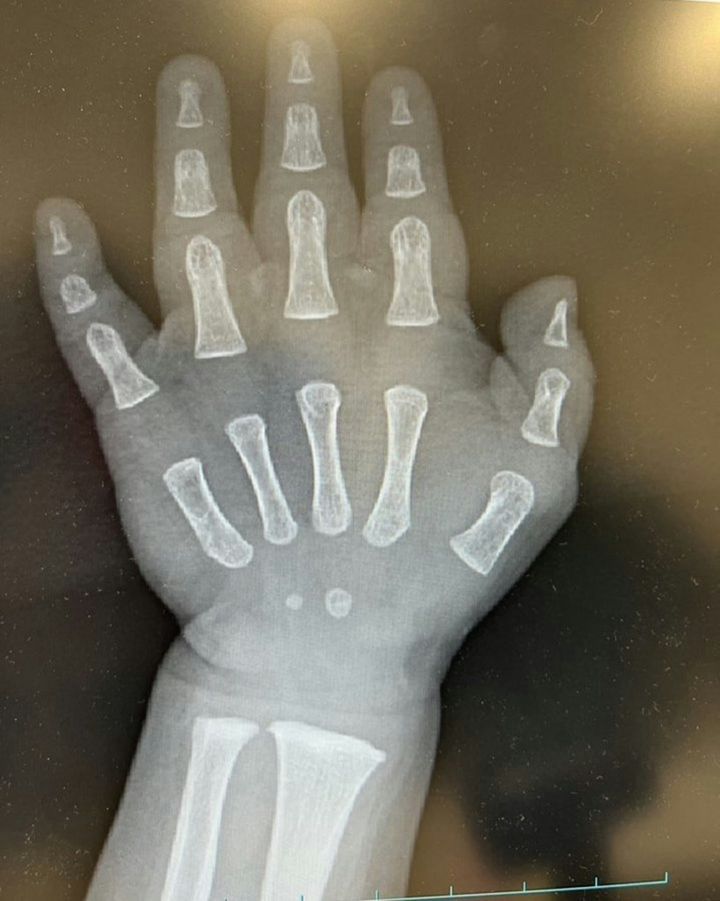

1歳の息子さんを育てる・うーさん🦖1y(@SakeLove_0403)さんは、息子さんの手のレントゲン写真を見て「骨がかわいいってどゆこと」と投稿。レントゲン写真までもかわいい、と話題となりました。大人とは違う、成長途中の小さな手が愛おしいお写真です。

ふっくらと丸みを帯びた手の形、小さく写った骨、どれをとっても愛おしいですね…。一見、骨と骨の間に隙間があり何もないように見えますが、軟骨はレントゲンに写らないので隙間があるように見えているだけなんだそうです。成長と共に骨もしっかりしてくるので、成長記録として思い出になりますね。

なお検査の為のレントゲンだったそうで、息子さんに怪我はなかったようです。

この投稿には「手首の「ちょんっ」しかない骨めっちゃかわいい」「むちむちのおててと、育ちきってない骨がたまらん…尊い…」といったコメントが寄せられていました。この小さな手が、骨が、これから大きく強く成長していくのだと生命の力強さを感じます。1歳の息子さんのレントゲン写真にキュンと癒される、素敵な投稿でした。